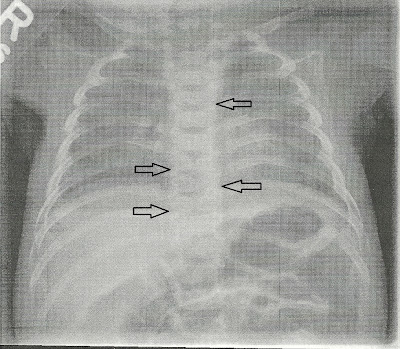

Медицина и здоровье: Синдром Титце и его диагностика